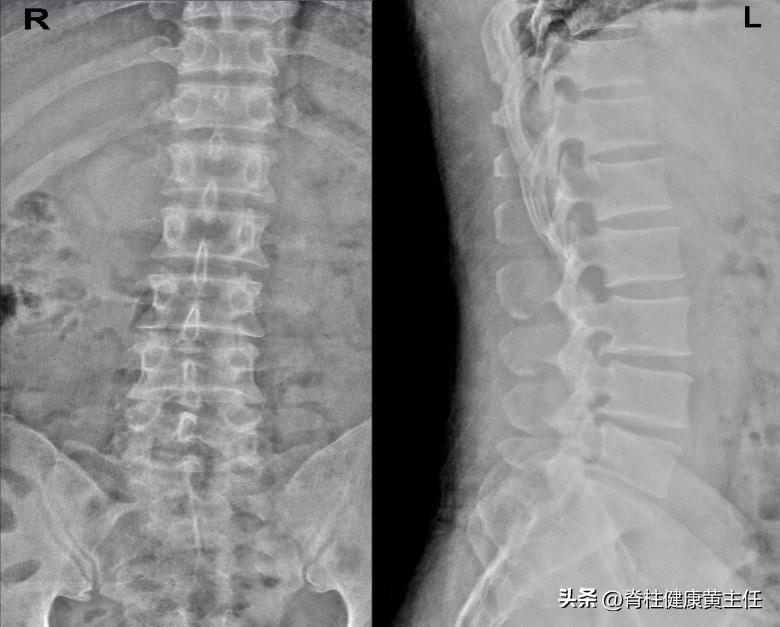

2023.03.12龙脊康腰椎X光阅片:腰椎生理期曲度存在,L3、L4、L5椎体骨质增生,骨刺形成,L4/5、L5/S1椎间隙明显多棘突偏歪。